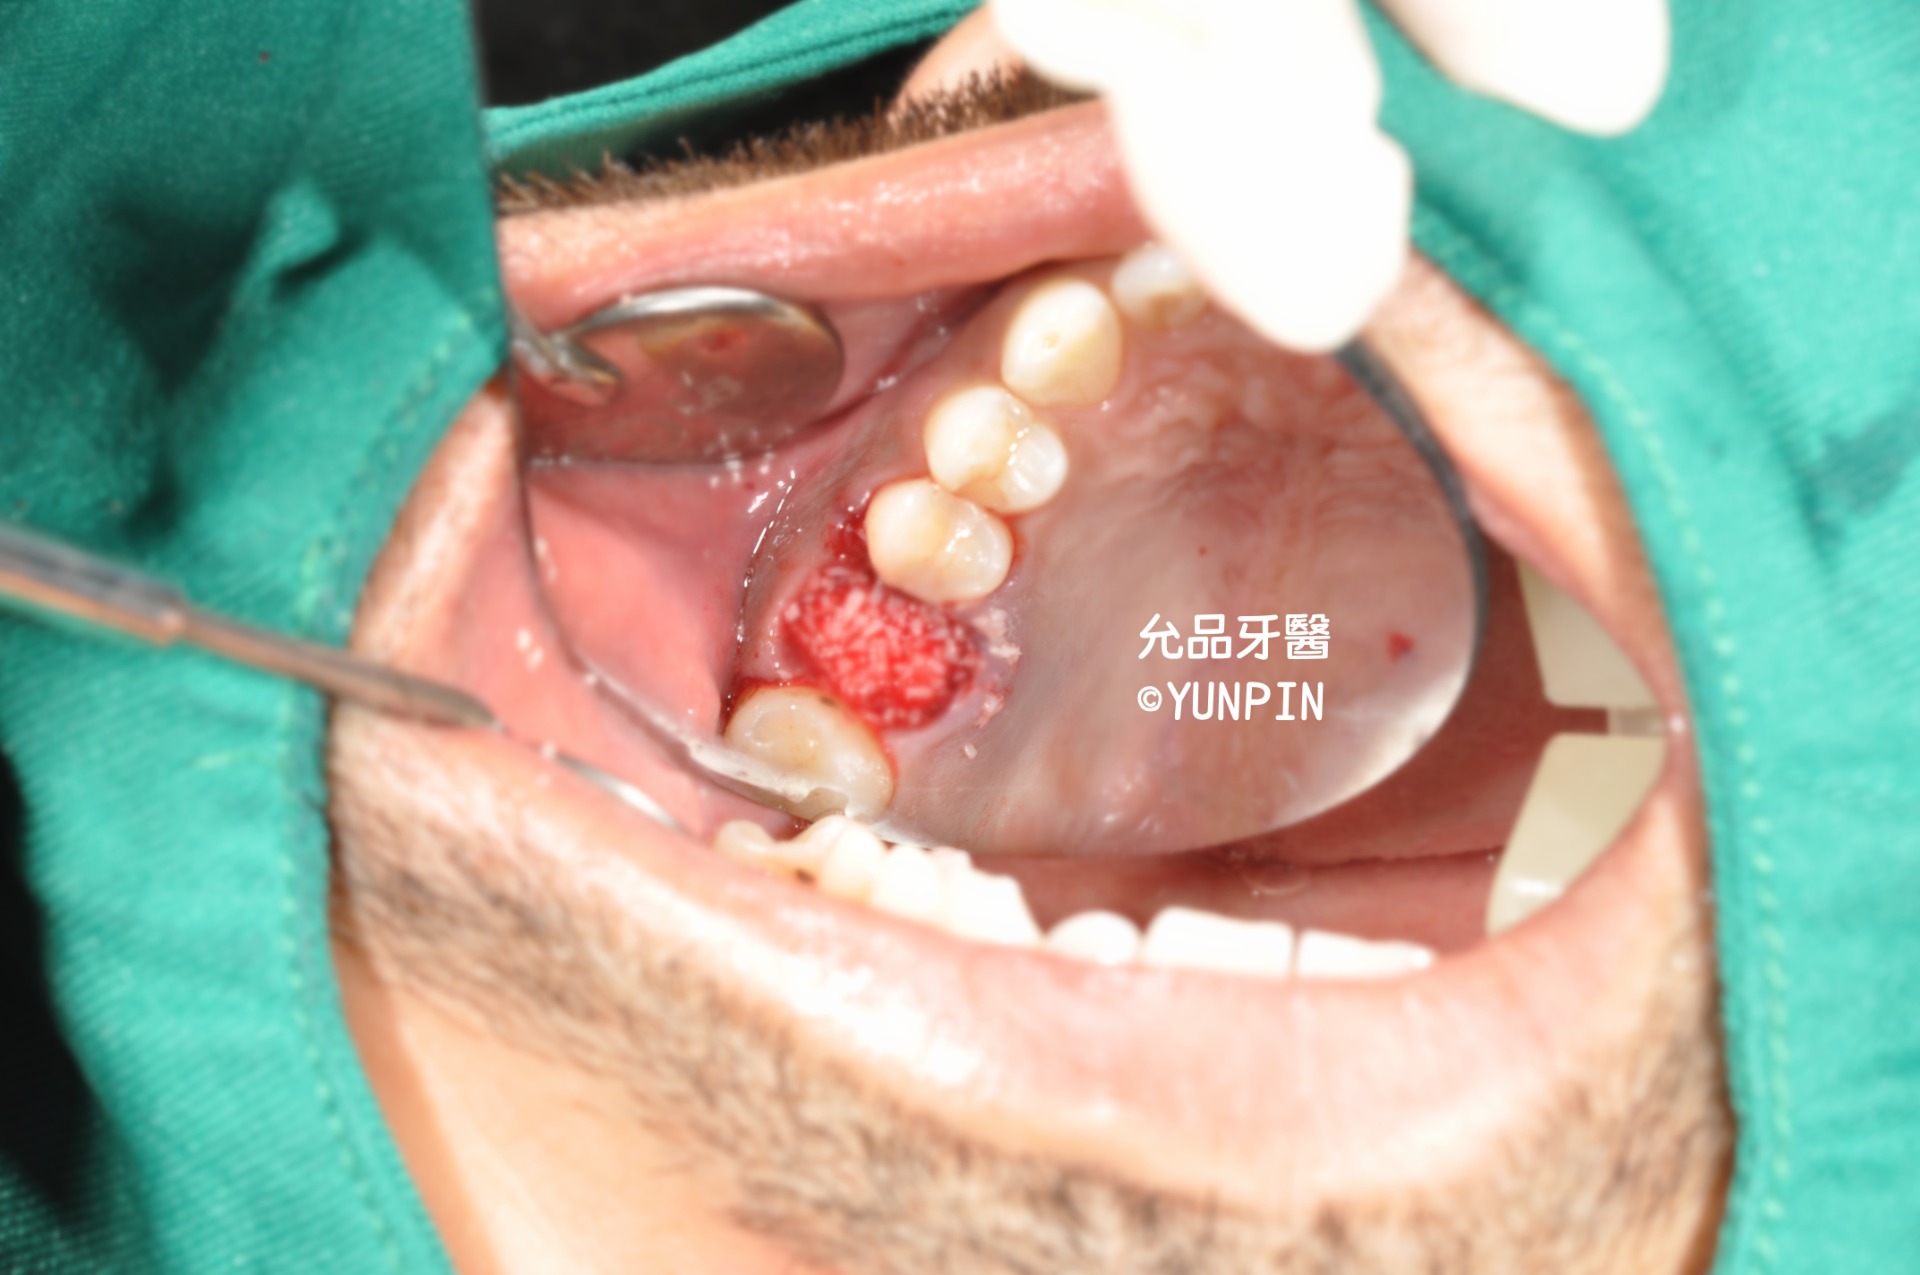

齒槽骨脊保存術socket preservation

患者主訴牙痛,他家診所檢查為牙裂,口內實際狀況已有明顯裂痕

討論完建議施作齒槽骨脊保存術,保留牙窩空間以利後續重建。